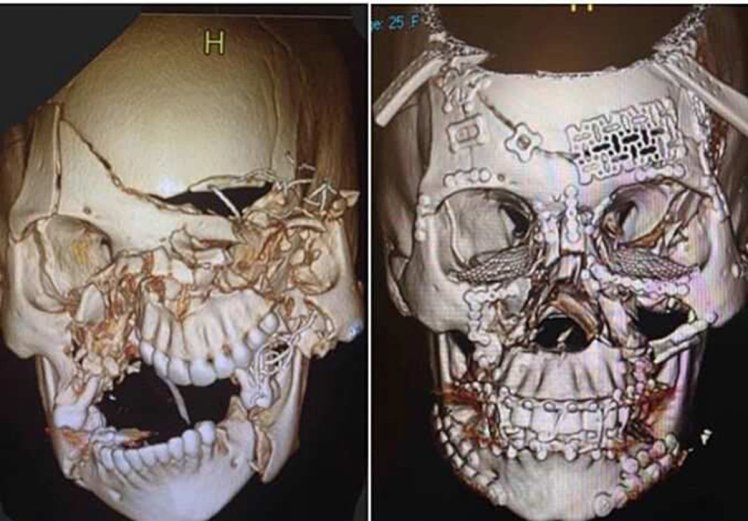

Η φωτογραφία που βλέπετε απεικονίζει το «πριν» και το «μετά» της εκτενούς αναδόμησης κρανίου στην οποία υποβλήθηκε μια γυναίκα, που φέρεται να ενεπλάκη σε τροχαίο ατύχημα.

Η εικόνα του διαλυμένου κρανίου της, όπως φαίνεται στις εικόνες που δημοσίευσε ένας εκ των χειρουργών της κάνει το γύρο του διαδικτύου για λόγους καθαρά εκπαιδευτικούς μήπως και με κάποιο τρόπο ευαισθητοποιηθούν συνειδήσεις

Δεν είναι γνωστό το τι ακριβώς συνέβη πριν η άτυχη γυναίκα φτάσει στο νοσοκομείο, αλλά κρίνοντας από τις φωτογραφίες, πρέπει να ήταν πολύ σοβαρό τροχαίο δυστύχημα.

Υπάρχουν αναφορές ότι πρόκειται περί γυναίκας που εμπλέκεται σε αυτοκινητιστικό ατύχημα και δεν φορούσε ζώνη ασφαλείας.

Όπως βλέπετε, δεν είναι μόνο η άνω και κάτω γνάθος που έχει διαλυθεί, αλλά το κρανίο έχει σπάσει και θρυμματιστεί σε διάφορα σημεία, με τα κομμάτια του απλώς να… επιπλέουν. Έχουν τοποθετηθεί σχεδόν παντού λάμες.

Ο επίσημος… κατάλογος των τραυματισμών της περιλάμβανε:

Τραυματική εγκεφαλική βλάβη με ενδοκρανιακή αιμορραγία

Τραυματικό των ματιών με εκτενές πρήξιμο

Εκτεταμένα κατάγματα προσώπου (άνω και κάτω γνάθος, ζυγωματικά κ.α.)

Εικόνα 1: Το «πριν»